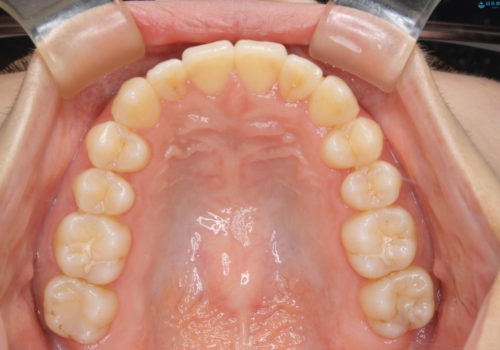

- 上の前歯が1本後ろに入ってしまっていることが気になるとご相談にいらした方です。

元々下の前歯が1本欠損しており、上下の噛み合わせや、歯のサイズバランスを考慮しながら治療を行いました。

クロスバイトしている歯が深く噛み込んでおり、この歯を外に出してくる際に強い咬合力が加わると歯が失活する恐れがあることを説明し、合わせて咬筋へのボトックス注入を行いました。

下顎切歯が1本欠損しているため、上顎前歯部を少しずつストリッピングして、上下の噛み合わせ、バランスの向上を図りました。